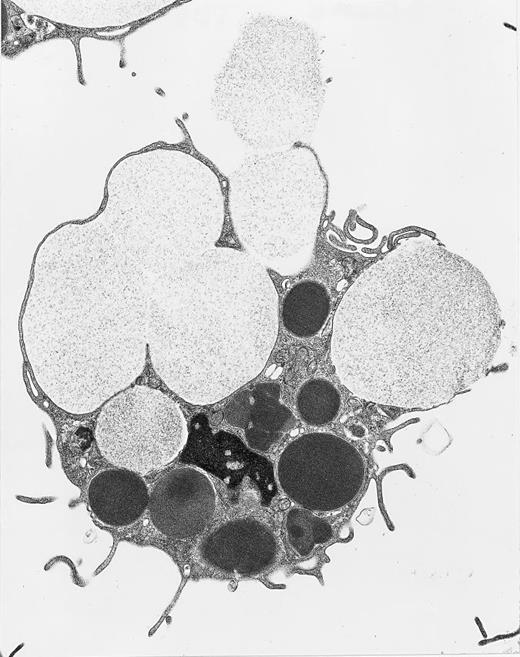

Peritoneal mast cell from a Beige rat undergoing anaphylactic degranulation of giant secretory granules. Swollen, less electron-dense secretory granules in the process of extrusion are enlarged beyond the giant, electron-dense cytoplasmic secretory granules not so involved. Original magnification × 12,000. (Courtesy of Ann M. Dvorak, MD, Department of Pathology, Beth Israel Hospital, Harvard Medical School, 330 Brookline Ave, Boston, MA 02215.)